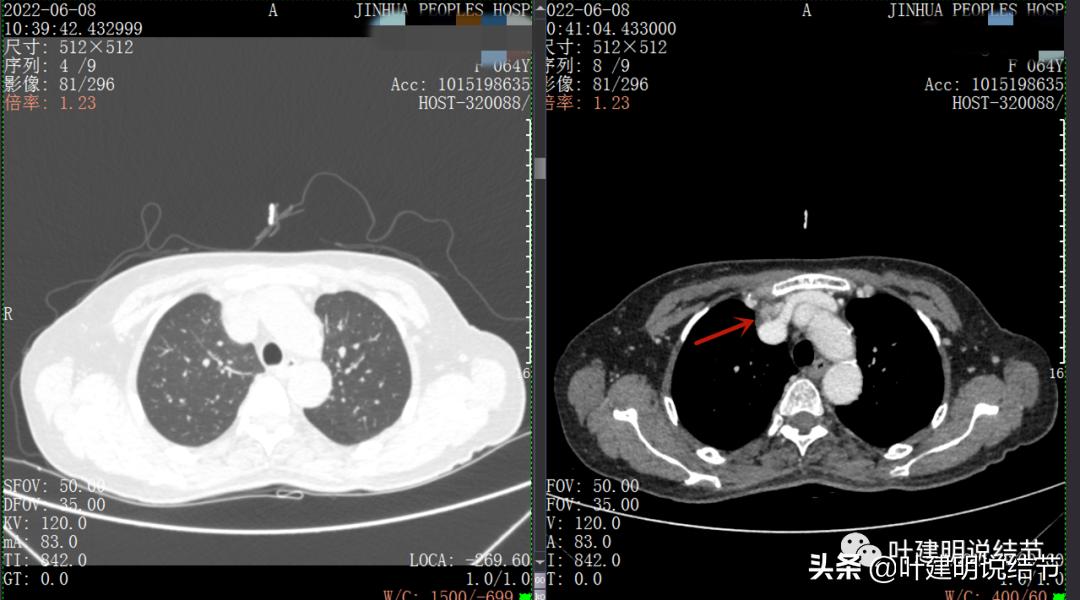

再来看看她的CT增强图像:

以下图片左侧是肺窗,右侧是纵隔窗。红色箭头示病灶,桔色箭头示无名静脉,黄色箭头示支气管,砖色箭头示上腔静脉,蓝色箭头示主动脉,紫色箭头示肺动脉。

病灶胸顶较高位置就出现了,在无名静脉水平

无名静脉略受压